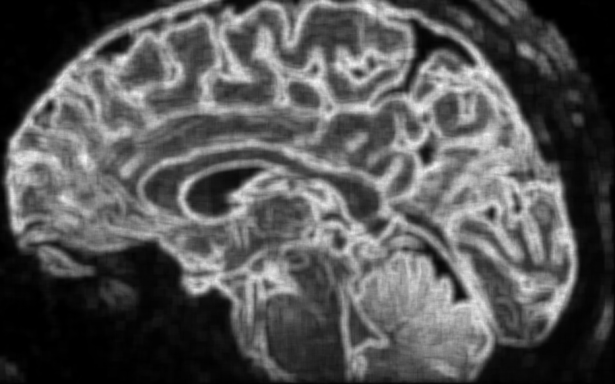

Médical

Voir n’est plus regarder : c’est comprendre la structure du monde cellulaire.

Loin du contraste classique, ϕ explore la richesse interne des tissus.

Elle distingue l’homogène du structuré, le bruit du sens, et redonne au regard médical une dimension topologique : celle de l’information vivante.

Les structures fines, souvent invisibles à l’œil nu, s’y dessinent comme des reliefs entropiques — un paysage du corps, révélé par la mathématique du vivant.